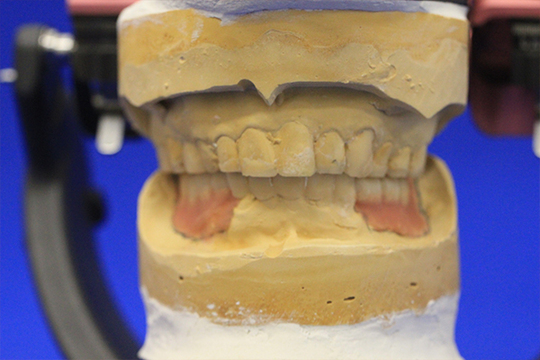

ディグマのデータを元に模型上で理想的な口腔内を再現します。